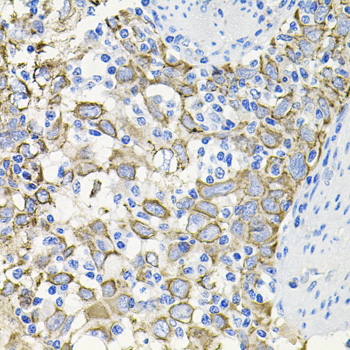

Immunohistochemistry of paraffin-embedded human lung using ACVR2A antibody at dilution of 1:100 (40x lens).

Immunohistochemistry of paraffin-embedded human esophageal cancer using ACVR2A antibody at dilution of 1:100 (40x lens).

Immunohistochemistry of paraffin-embedded mouse brain using ACVR2A antibody at dilution of 1:100 (40x lens).